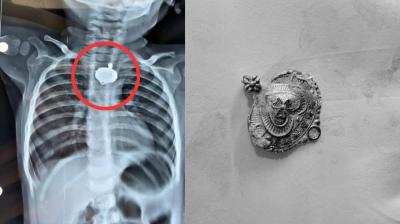

बड़वानी में 9 माह के बच्चे की आहार नली में फंसा मंगलसूत्र, डेढ़ महीने बाद एक्स-रे से खुलासा

बड़वानी: रविवार को जिला अस्पताल में एक बेहद संवेदनशील और हैरान करने वाला मामला सामने आया. जब 9 माह के एक बच्चे के गले में मंगलसूत्र फंसा हुआ देखा गया. घटना...